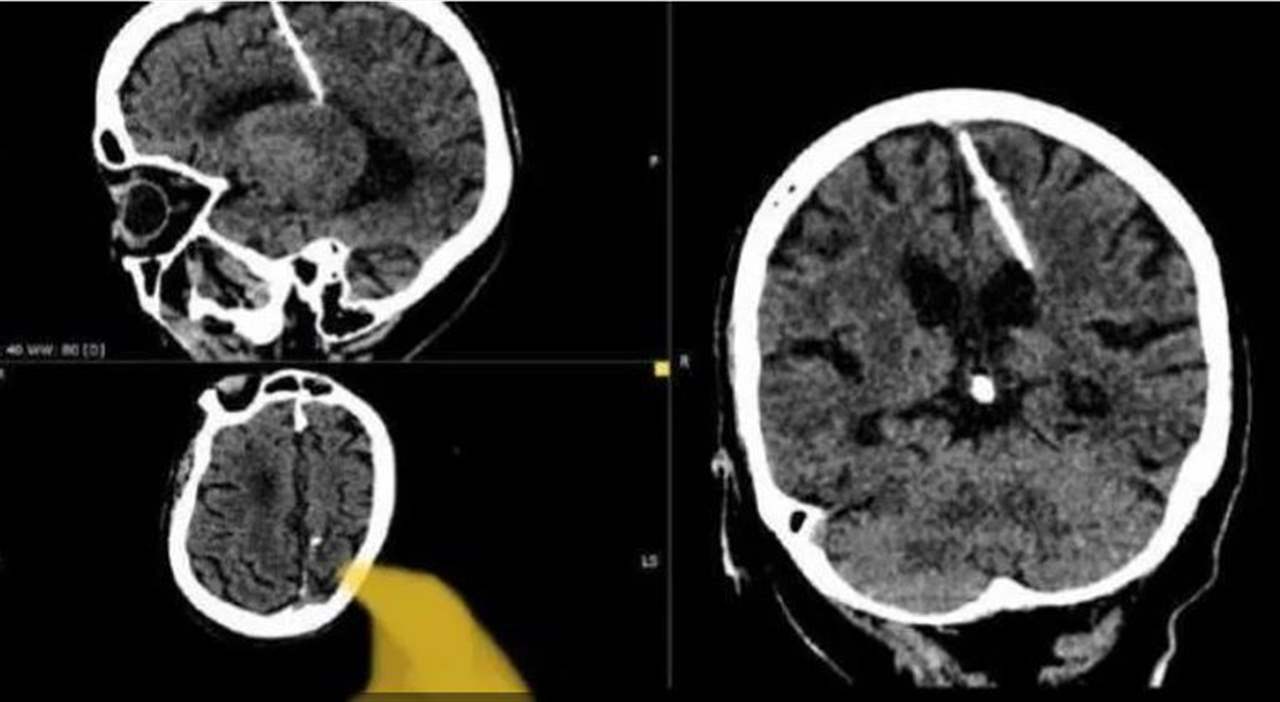

بالصورة - العثور على إبرة في رأس امرأة

عثر أطباء خلال فحص بالتصوير المقطعي على إبرة بطول ثلاثة سنتيمترات موجودة منذ ثمانين عاماً داخل دماغ امرأة مسنّة في أقصى الشرق الروسي.

ويعتقد الأطباء أن المرأة تعرضت لمحاولة قتل فاشلة نفذها والداها خلال طفولتها، وقالوا إنهم لن يحاولوا إزالة الإبرة خشية أن يفاقم ذلك حالتها.

وقالت إدارة الصحة المحلية في منطقة سخالين الروسية النائية إنّ "مثل هذه الحالات كانت شائعة خلال سنوات المجاعة".

وأضافت أن والديها قررا على الأرجح التخلص من طفلتهما خلال الحرب العالمية الثانية، لأنها كانت تعيش مع إبرة يبلغ طولها ثلاثة سنتيمترات "منذ ولادتها".

ولفتت إلى أن هذه الطريقة كثيرا ما تُستخدم لإخفاء أدلة الجريمة.

وكان نقص الغذاء سائداً في جميع أنحاء الاتحاد السوفياتي خلال الحرب، وعاش الكثير من السكان في فقر مدقع.

وقالت إدارة الصحة المحلية "لقد اخترقت الإبرة الفص الجداري الأيسر، لكن لم يكن لها التأثير المقصود، إذ نجت الفتاة".

وأضافت أن المريضة لم تشكُ قط من الصداع بسبب الإصابة، ولم تكن تواجه أي خطر، لافتة إلى أن "حالتها تحت مراقبة الطبيب المعالج".